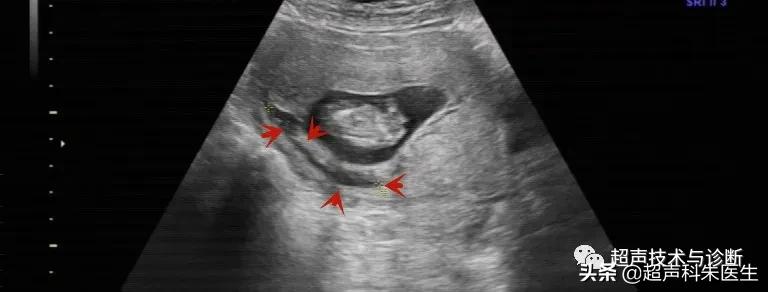

出现绒毛膜下血肿的孕妇,仅有20%会出现阴道不规则流血或下腹部疼痛的症状,而其余大多数绒毛膜下血肿是在超声检查中发现的,其超声表现为:子宫壁和胎膜(或孕囊)之间的无回声区,多位于胎盘下缘至宫颈内口间,以弧形或新月形多见,若血肿较多或血肿形成时间较长时,内可见点、絮状弱回声及条带状强回声,彩色多普勒超声检查:血肿内无血流信号。

接下来我们来看看具体病例:

绒毛膜下血肿需要注意和羊膜绒毛膜未融合以及胎盘早剥进行鉴别。①羊膜绒毛膜未融合是一种现象,在妊娠初期,胚外体腔相对较大,而羊膜囊和卵黄囊均较小,而随着胚胎的发育,羊膜囊逐渐增大,羊膜与绒毛膜越来越靠近,胚外体腔也随之减小,于14周左右羊膜与绒毛膜相互融合,此时胚外体腔消失,若14周后羊膜与绒毛膜之间的距离≥3mm,此情况即为羊膜绒毛膜未融合。②胎盘早剥发病急,有腹痛,血肿位于胎盘后方与子宫壁之间。